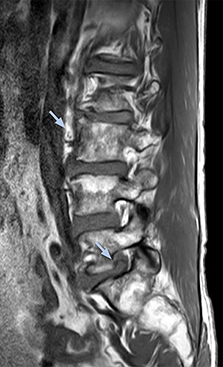

“Before NerveVIEW, diagnosis by MRI alone was sometimes difficult, unless there was a strong suspicion based on clinical symptoms,” says Shoji Yabuki, MD, DMSc, Orthopedic surgeon at Fukushima Medical University School of Medicine. “This is why we routinely perform selective lumbosacral radiculography (nerve root block) and x-ray in such cases. However, radiculography can only depict nerves as far as the contrast agent reaches. When a nerve is distorted by compression, the contrast agent will not pass through this compressed area, preventing us from evaluating the full nerve compression.”

The key concept in MR neurography, Dr. Yabuki stresses, is the ability to directly visualize spinal nerves, versus inferring the presence of pathology indirectly. “Before NerveVIEW, we estimated compression of the nerve by looking for the presence or absence of fat signal on other MR images,” he says.

“For example, in sagittal images, when the presence of fat is observed in the intervertebral foramen, it suggests that there is a margin around the nerve. Similarly, the absence of fat indicates that the nerve is being compressed. So, we used to deduce nerve compression indirectly. With NerveVIEW, however, we can observe the condition of the nerves directly, regardless of the presence or absence of fat. We always prefer such direct observation of anatomy over having to make an inference about it.”

“Although symptoms of typical disc herniation and atypical hernia are very similar, the actual site of herniation is different. It is therefore important to characterize the nerve’s condition both inside and outside of the intervertebral foramina. “Conversely, if we see no abnormality in NerveVIEW, we can assume at least that there is no severe condition that requires surgery. Like this, it can help us avoid unnecessary surgery. NerveVIEW can have a tremendous impact in this way.”

“NerveVIEW is really useful for those cases where a nerve disorder is strongly suspected based on the clinical examination but our regular MRI images do not show any findings. These atypical herniations and spinal canal stenosis, occurring in 5% to 15% of the total lumbar herniation/stenosis cases are our main target when using NerveVIEW,” says Dr. Yabuki.